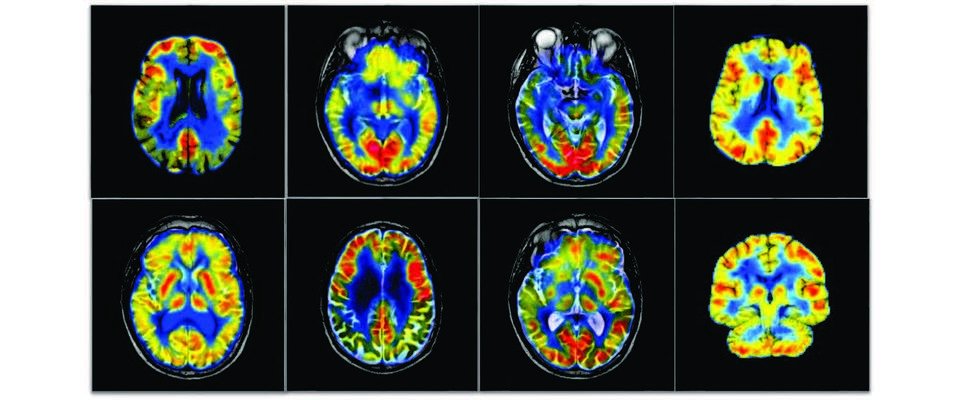

Delighted to share our new study with colleagues at UCL (UK), the University of São Paulo (USP) and UNIFESP in Brazil. We show that regular, moderate aerobic exercise appears to “rewire” the sympathetic nerves that drive the heart — and it does so differently on the left and right side. Using advanc...